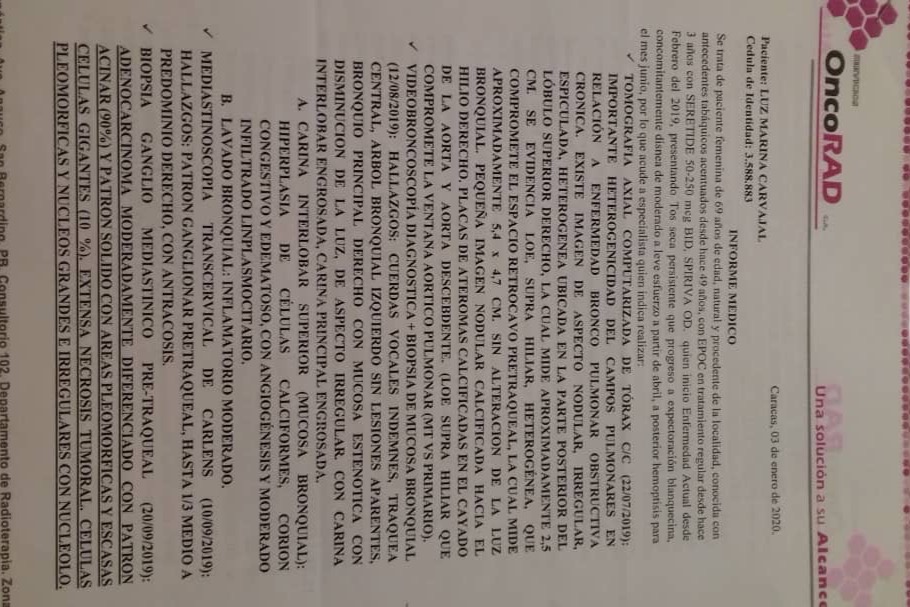

En septiembre de 2019 fue diagnosticada con cáncer de pulmón con una Lesión Ocupante de Espacio (LOE) de 2,5 cm y otra lesión en el Mediastino de 5,4 x 4,7 cm.

A través de varios familiares hemos logrado conseguir dinero para realizarle 36 ciclos de radioterapia y 6 de quimioterapia, además del tratamiento y todos los medicamentos requeridos hasta ahora, logrando una reducción importante del tamaño del tumor en pulmón en 40 %. Gracias a Dios la lesión en el mediastino se redujo también en un 80%.

A continuación les dejo el diagnóstico, los exámenes, y los presupuestos de los próximos exámenes que hay que hacerle a mi mamá.

In September 2019, she was diagnosed with lung cancer with a Space Occupying Injury (LOE) of 2.5 cm and another lesion in the Mediastinum of 5.4 x 4.7 cm.

Through several family members we have managed to raise money to perform 36 cycles of radiotherapy and 6 of chemotherapy, in addition to the treatment and all the medications required so far, achieving a significant reduction in the size of the tumor in the lung by 40%. Thank God the injury to the mediastinum was also reduced by 80%.

Down here I leave the diagnosis, exams, and budgets for the next exams to be done to my mom.